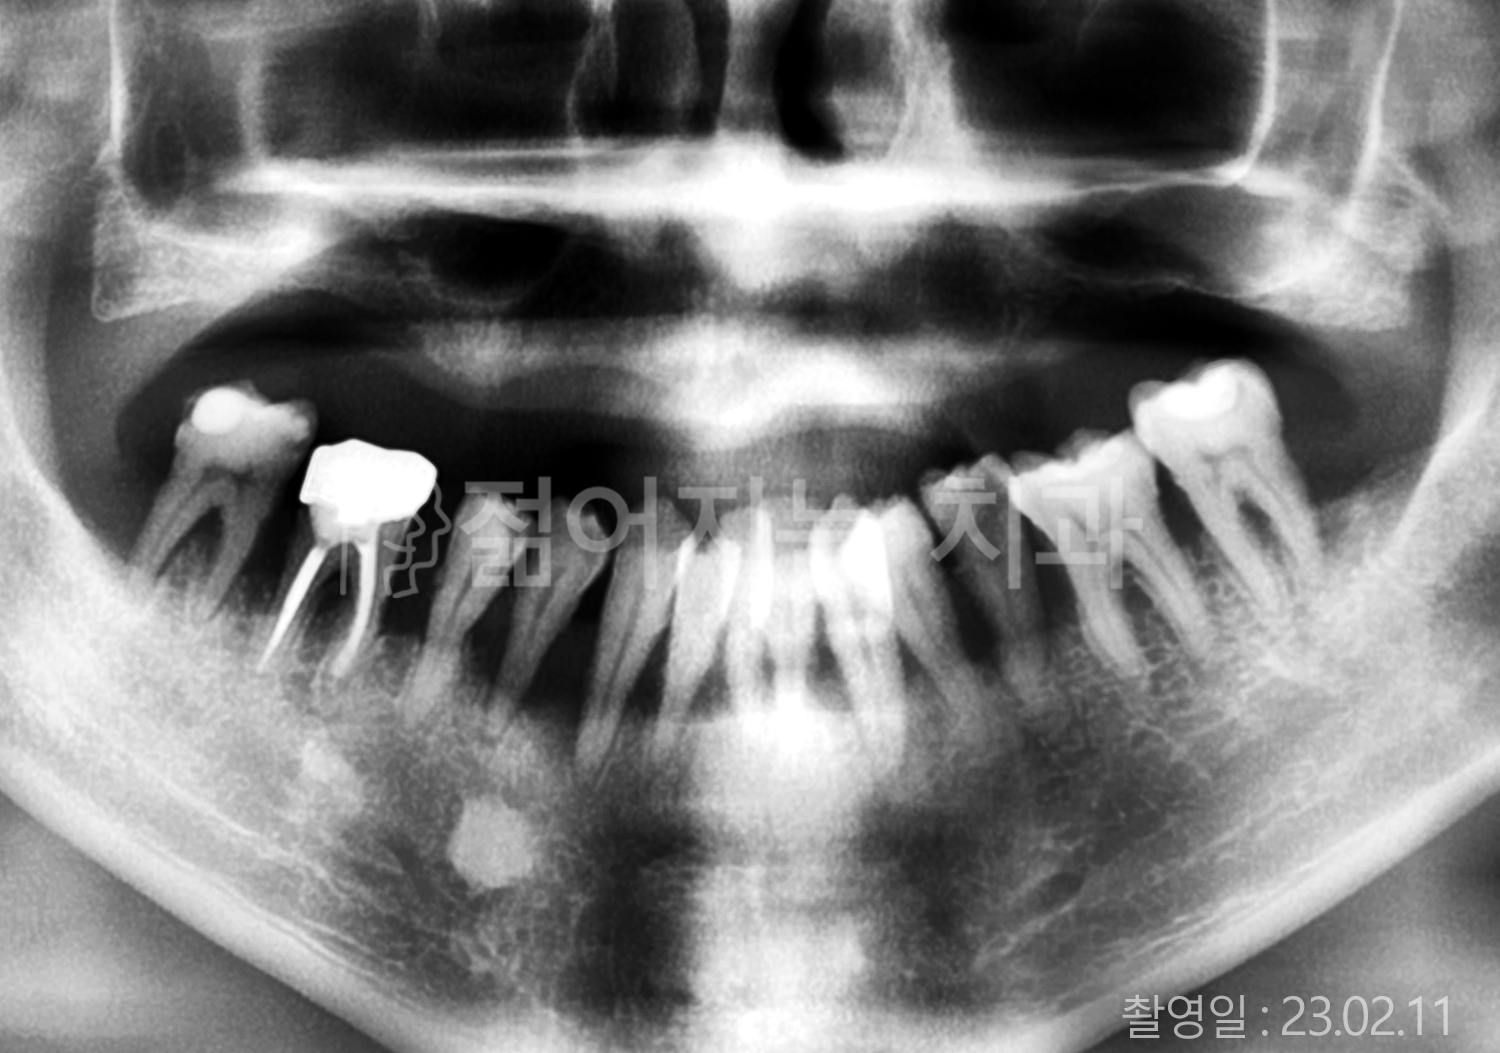

• 80대 전체치아 10개 이상 임플란트

• 60대 고혈압, 당뇨, 고지혈증 전체치아 10개 이상 임플란트

• 60대 전체치아 10개 이상 임플란트

• 60대 고혈압, 고지혈증 전체치아 10개 이상 임플란트

• 50대 고혈압, 당뇨, 고지혈증 전체치아 10개 이상 임플란트

• 70대 골다골증, 파킨스병 전체치아 10개 이상 임플란트

• 40대 전체치아 10개 이상 임플란트

• 60대 골다골증 전체치아 10개 이상 임플란트

• 40대 고혈압 전체치아 10개 이상 임플란트

• 50대 전체치아 10개 이상 임플란트

• 70대 전체치아 10개 이상 임플란트